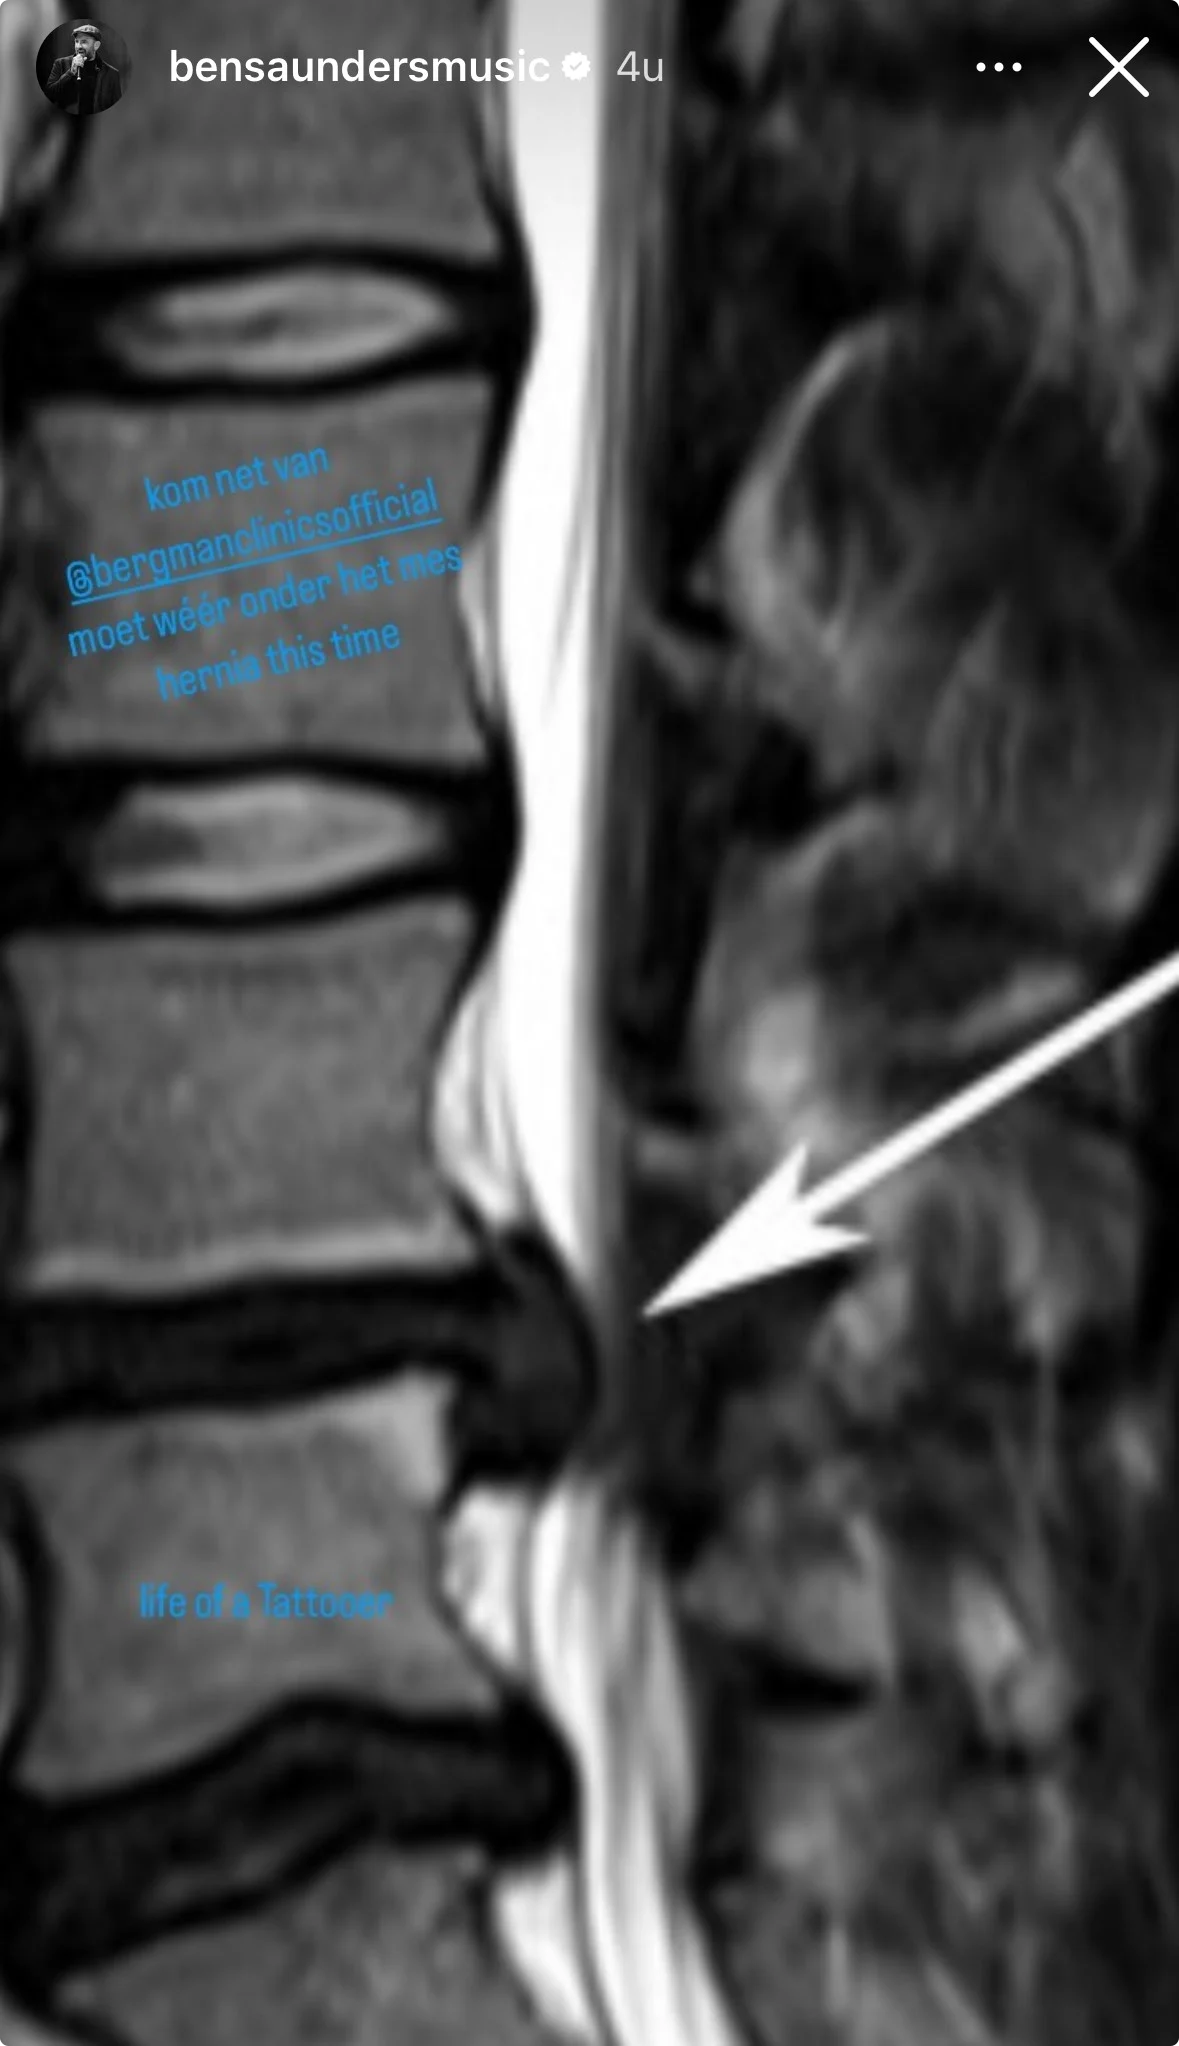

"Kom net uit de kliniek en moet wéér onder het mes", zo schrijft Ben in zijn Instagram Stories. "Hernia deze keer." Hij deelt een foto van de röntgenfoto van zijn rug.

Door middel van een pijl wil hij duidelijk maken waar de hernia zit. Hij schrijft daarbij: "Het leven van een tatoeëerder." Daarmee denkt hij dat het waarschijnlijk komt door zijn werk als tatoeëerder.